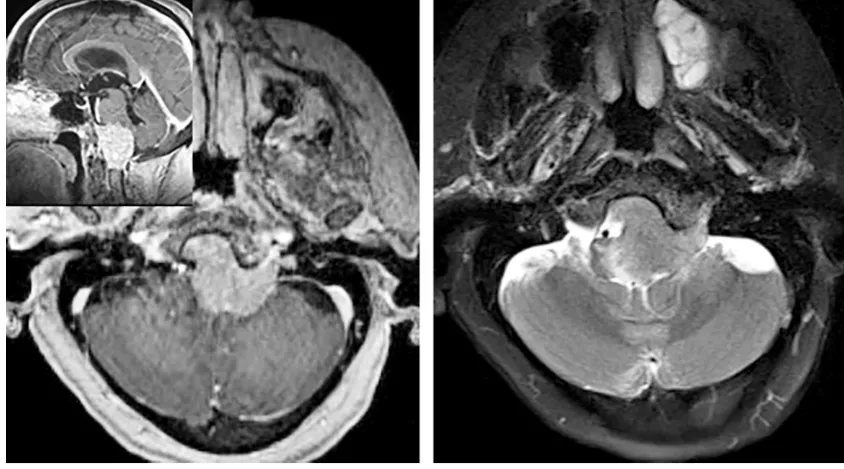

同时,MRI矢状位和冠状位图像可直接显示延髓、颈髓受压情况。当肿瘤侵犯脑干软脑膜时,T2加权像可见脑干区域高信号改变,FLAIR像表现更为明显,这常提示脑水肿存在,肿瘤压迫脑干导致水肿往往影响肿瘤切除程度及术后并发症发生。增强结果可反映肿瘤血供情况,轴位及冠状位图像也有助于判断肿瘤与同侧椎动脉及周边硬脑膜的关系。MRI也是鉴别枕骨大孔区肿瘤与颈椎病、寰枕畸形等重要手段。

图示:枕骨大孔脑膜瘤伴脑干水肿提示软脑膜受累,此时应考虑次全切除以保护神经功能。